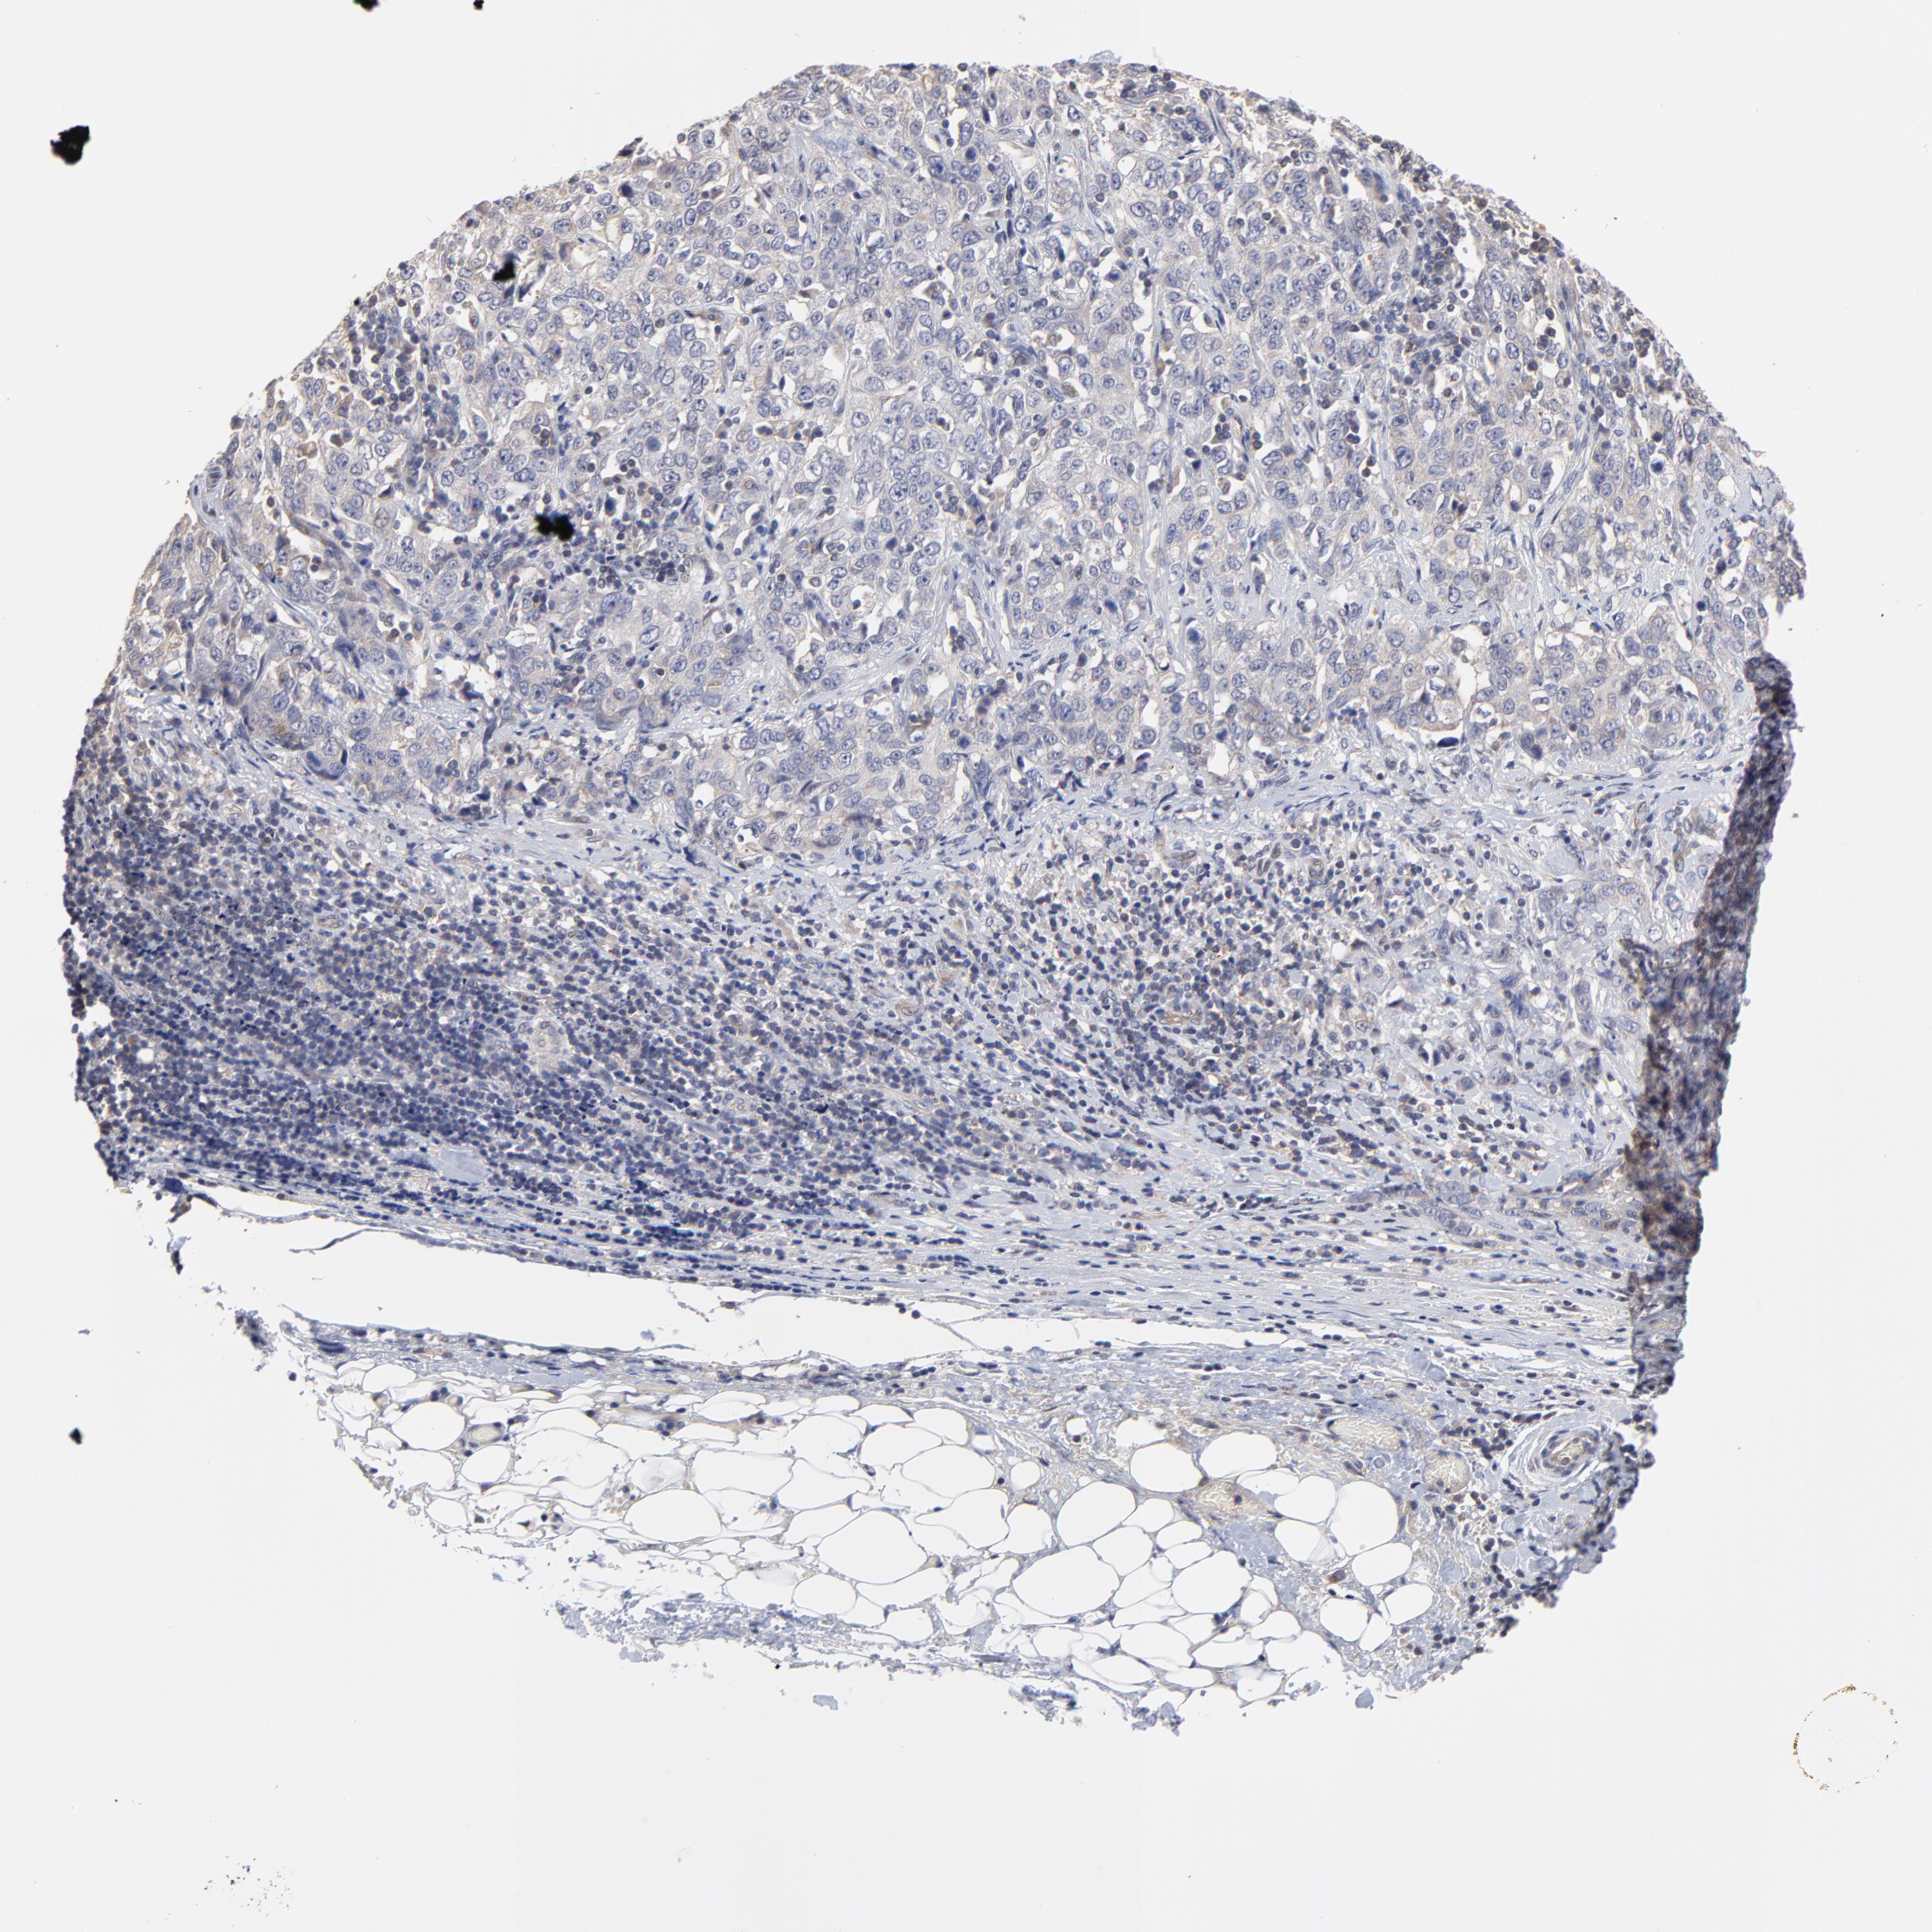

STOMACH CANCER - Protein expressioni

A mouse-over function shows sample information and annotation data. Click on an image to view it in a full screen mode. Samples can be filtered based on level of antibody staining by selecting one or several of the following categories: high, medium, low and not detected. The assay and annotation is described here.

Note that samples used for immunohistochemistry by the Human Protein Atlas do not correspond to samples in the TCGA dataset.

Antibody stainingi

Antibody staining in the annotated cell types in the current human tissue is reported as not detected, low, medium, or high, based on conventional immunohistochemistry profiling in selected tissues. This score is based on the combination of the staining intensity and fraction of stained cells.

Each image is clickable and will lead to virtual microscopy that enables deeper exploration of all samples and also displays staining intensity scores, fraction scores and subcellular localization as well as patient and tissue information for each sample.

Antibody HPA003319

Staining

High

Medium

Low

Not detected

Intensity

Strong

Moderate

Weak

Negative

Quantity

>75%

75%-25%

<25%

None

Location

Nuclear

Cytoplasmic/membranous

Cytoplasmic/membranous,nuclear

Adenocarcinoma, NOS

Adenocarcinoma, High grade